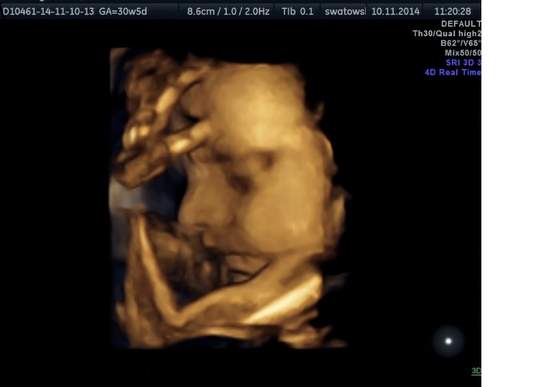

My dzisiaj też byłyśmy na usg. Wszystko dobrze, mała nadrobiła zaległości i już jest pare dni większa niż wskazuje termin. Wazy 1700g.

Alutka1.jpg

• Alutka1.jpg

12,6 KB · Wyświetleń: 74